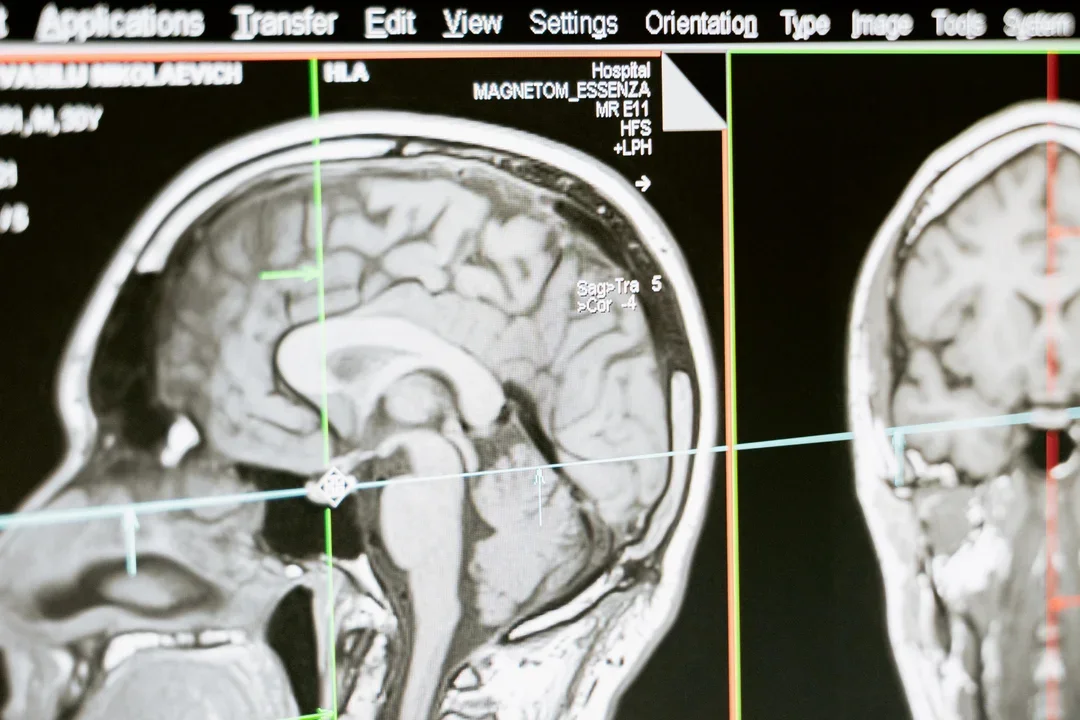

Gwałtownie rośnie liczba niedokrwiennych udarów mózgu. Będzie ich jeszcze więcej. Sprawdź, czy jesteś w grupie ryzyka

Średnio co 6,5 minuty ktoś w Polsce doznaje udaru mózgu. To pierwsza przyczyna trwałej niepełnosprawności wśród dorosłych Polaków. | foto pexels

LifestyleRocznie nawet 90 tys. Polaków doznaje niedokrwiennego udaru mózgu. Ale to nieprawda, że ataki przytrafiają się tylko starszym ludziom. Mitem jest także, że młodsi mają większe szanse z nich wyjść. Ofiarą choroby może zostać każdy. Bez względu na wiek.

Jak mówi nam dr Marta Bott-Olejnik, neurolog pracująca na co dzień na oddziale neurologicznym w szpitalu w Gryficach, w Polsce co 6,5 minuty doznaje ktoś udaru mózgu. Blisko 75 procent ataków to właśnie udary niedokrwienne. Ale młodzi ludzie myślą, że statystyki ich nie dotyczą. Tymczasem – choć dokładnych danych na razie brak – lekarze mówią głośno, że choroba dotyka coraz więcej osób jeszcze przed trzydziestką. Chorują nawet nastolatkowie. Szacuje się, że do roku 2030 udar mózgu będzie stanowić jeden z najpoważniejszych problemów medycznych.